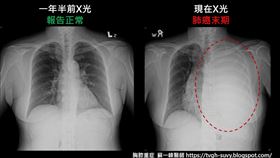

沒抽菸仍中鏢!女師肺癌亡 醫揭做1事保命

肺癌是國人最常見的癌症之一。許多人認為不抽菸就不會得...